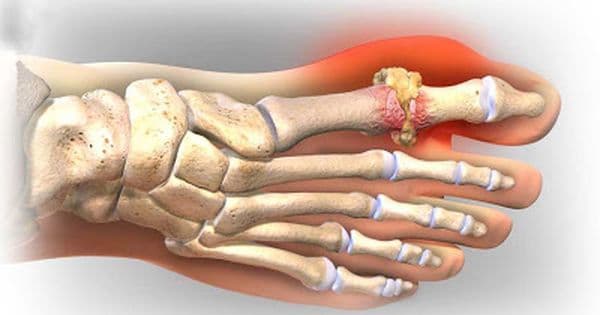

Triệu chứng bệnh gout không thể bỏ qua

Bệnh gout là bệnh do rối loạn chuyển hóa purin làm tăng lượng acid uric trong máu. Nếu không được điều trị kịp thời, hiệu quả, bệnh có thể tiến triển gây nên biến chứng nguy hiểm. Dưới đây là những triệu chứng bệnh gout không thể bỏ qua. Triệu chứng cảnh báo bệnh gout […]